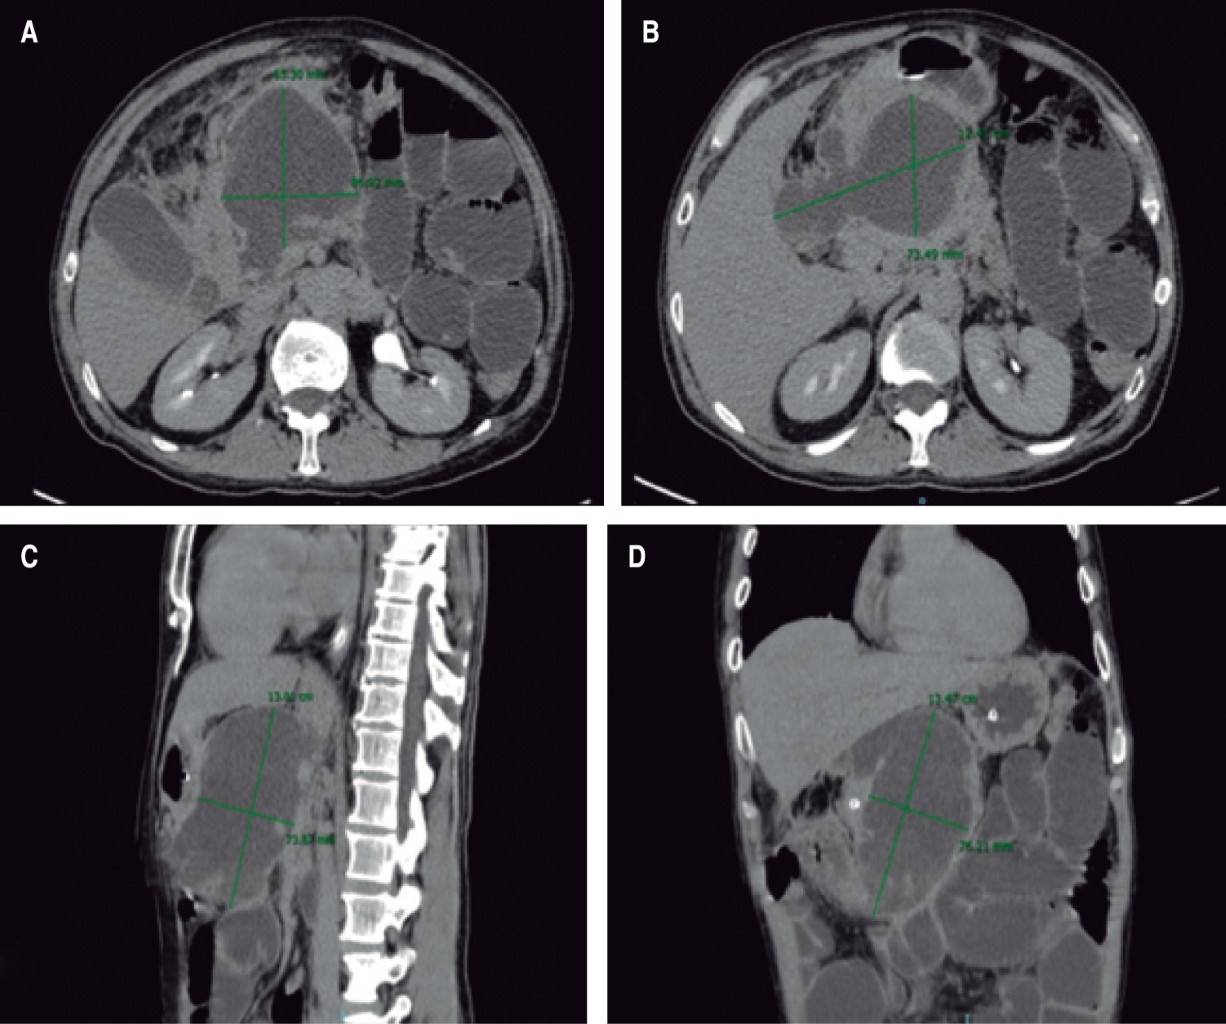

A 48-year-old male patient with a history of smoking (TI of 23), intense alcoholism, marijuana use, hepatitis C, and a history of two events of mild acute pancreatitis of alcoholic origin resolved without apparent complications. Two and a half months later, he came to the emergency department for abdominal pain, presenting hyporexia, nausea, and vomiting after two days of evolution, finding on physical examination pain and increased volume on palpation at the epigastric level located at deep planes, with no evidence of peritoneal irritation. The diagnostic protocol was completed documenting moderately severe acute alcoholic pancreatitis. A computed axial tomography (CT) scan showed evidence of hypodense and irregular image measuring 13.47 × 12.41 × 8.53 cm, with a defined wall and heterogeneous content corresponding to a pancreatic pseudocyst of 746 ml of volume (Figure 1). He started with supportive management until the remission of acute pancreatitis. Laparoendoscopic cystogastric bypass was performed, with findings of a pancreatic pseudocyst with septated necrotic content, which displaced the stomach, obtaining a total of 700 mL of cloudy liquid and detritus (Figure 2). A triple lumen nasojejunal tube was placed for immediate enteral feeding and gastric decompression. The patient was discharged in two days from the General Surgery Service of the Centenario Hospital "Miguel Hidalgo" with a nasojejunal tube and outpatient control, which was removed three weeks after the surgical event, adequately tolerating the oral route.

Figure 1